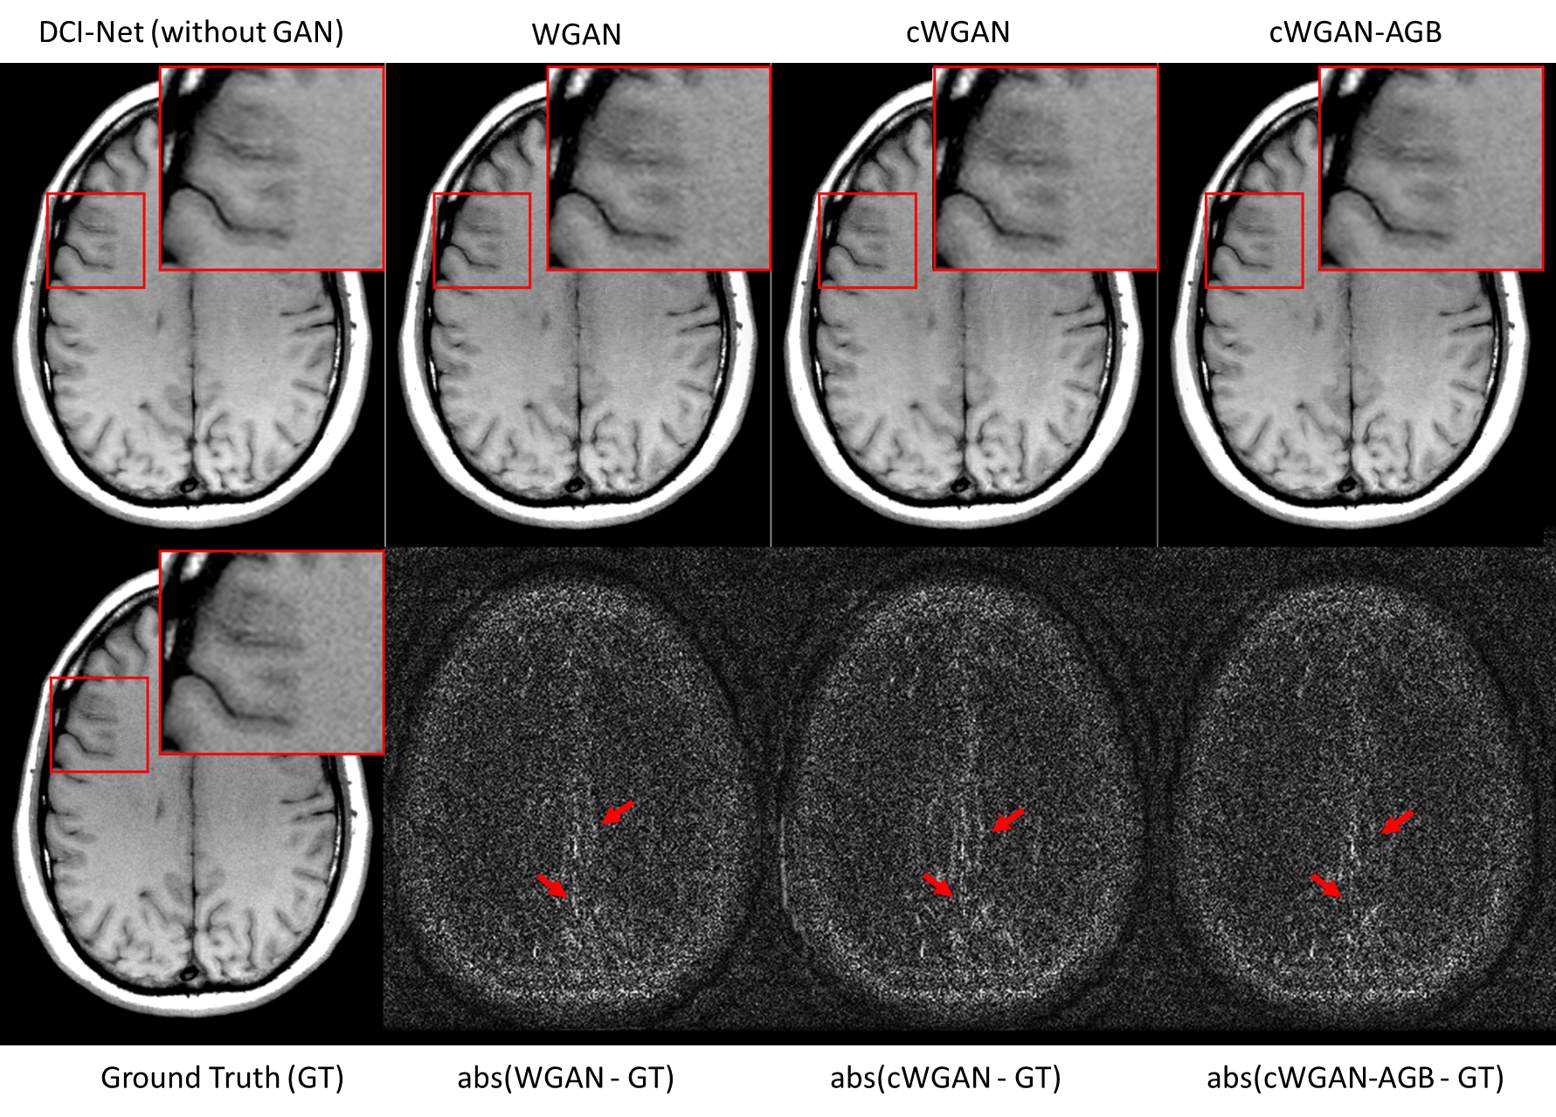

6.5 Ablation Analysis

We compare, in Table III, our cWGAN-AGB with three other models: 1) cWGAN, 2) WGAN, and 3) a baseline DCI-Net for undersampled MRI reconstruction, which optimizes an MSE loss alone without any GAN. All models were evaluated with NMSE and FID on the test set. We found that (a) cWGAN and cWGAN-AGB have better SNR than WGAN, (b) cWGAN-AGB converges much faster than cWGAN or WGAN (Fig. 12), has fewer artifacts, and performs better in both FID and NMSE measures (Table III) and (c) although cWGAN-AGB has higher NMSE than the baseline DCI-Net, it performs better in FID and yields sharper images with more fine details while maintaining a natural image texture. A representative reconstruction can be seen in Fig. 13, where both WGAN and cWGAN models suffer from local inconsistencies with the ground truth image (red arrows). In the same area, our proposed method exhibits a more accurate reconstruction. In addition, Fig. 13 shows a representative reconstruction from the baseline DCI-Net (trained without GAN loss), which exhibits some image blurring.

In Table III, we also compare to baseline architectures, demonstrating the effectiveness of our key new architecture developments: (1) dense connections across all iterations, which strengthen feature propagation, making the network more robust, and (2) a relatively deep architecture of 20 iterations, comprising more than 60 convolutional layers, which brings increased capacity. We compared our generator to (1) an unrolled iterative network, similar to DCI-Net but without dense connections and (2) a 5-iteration DCI-Net with a similar number of learned parameters. Employing dense connections significantly improved accuracy, and the deeper network produced 12% lower mean NMSE than a shallower network with a similar number of learned parameters.

6.6 Visual Scoring

To assess the perceptual quality of the resulting images we report a visual scoring conducted by four experienced MRI scientists. The same test set was ranked for cWGAN-AGB, the baseline DCI-Net and for the fully sampled images. The scoring was performed blindly and the images were randomly shuffled. The studies were taken from a cohort of seven healthy volunteers. Each study contained a full brain scan comprising 25-43 slices. For each study, image sharpness, signal-to-noise ratio (SNR), contrast, artifacts and overall image quality (IQ) were reported. Here images were rated on a scale of 1 to 5, where the numbers denote 1: not diagnostic, 2: limited, 3: diagnostic, 4: good, 5: excellent. Table III shows that cWGAN-AGB produced significantly sharper images than the baseline DCI-Net, at the cost of somewhat weaker denoising of the images.